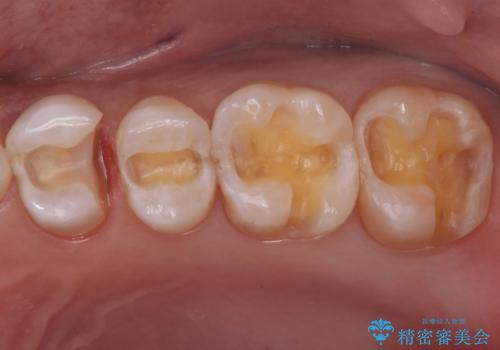

銀歯と樹脂の詰め物のやり替え セラミックインレーでの治療

- 奥歯の詰め物のやり替え希望で来院されました。

残る歯の量が多かったためすべてインレーでの治療となりました。